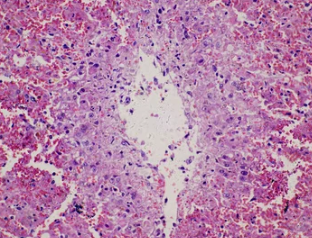

- 조직 검사: 폐 조직을 채취하여 섬유화 정도를 분석합니다.